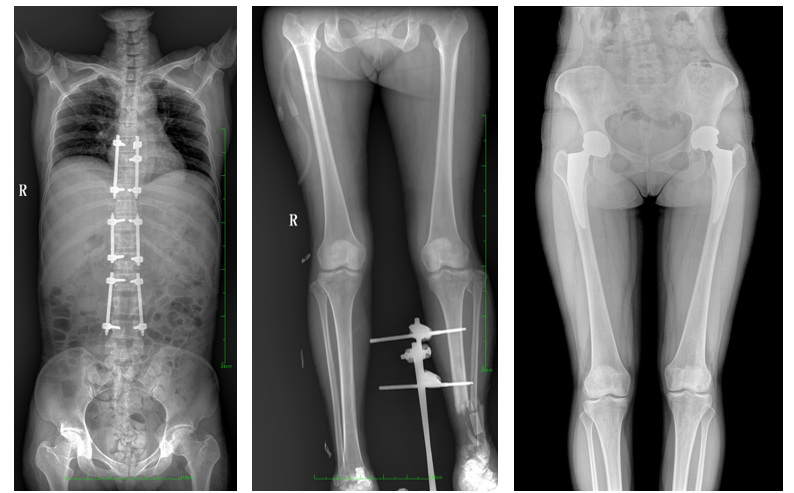

一、成像面積大。17"*34"有效視野,一次成像不拼接。相較于多張攝影再軟件拼接的DR設(shè)備,大視野平板動態(tài)DR解決了拼接圖像存在密度不均勻,拼接處圖像配準(zhǔn)和放大效應(yīng)等問題,給臨床帶來了大視野影像解決方案,可一次性覆蓋全脊柱或雙下肢影像。

如:全脊柱狀態(tài)評估、長骨關(guān)節(jié)活動度、下肢靜脈造影瓣膜功能評估、消化道功能評估、脊髓造影等更多大視野臨床應(yīng)用,多面手給醫(yī)生更多驚喜。

PLX8600大視野平板動態(tài)DR可在低輻射劑量下獲得患者站立位、臥位的高質(zhì)量影像。搭載自主研發(fā)的圖像均衡處理系統(tǒng),能夠很好的均衡人體不同厚度組織的影像,視野大,圖像清晰,層次豐富。